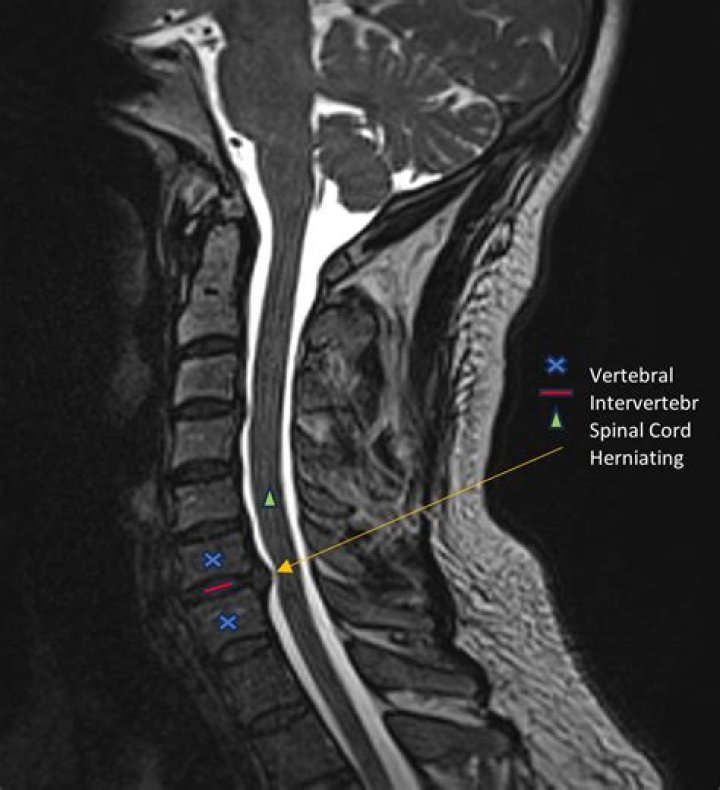

Clinical Series: How to See a Pinched Nerve (Foraminal Stenosis) on MRI

MRI scans which show soft tissues, such as nerves and discs, are generally preferred over CT scans which show bony elements. Advanced imaging can show exactly which nerve or nerves are being pinched and what is causing the nerve to be pinched.

MRIs are able to provide in-depth information on not only the spinal cord but individual nerves as well. There is a good chance that an MRI should be able to detect a pinched nerve.